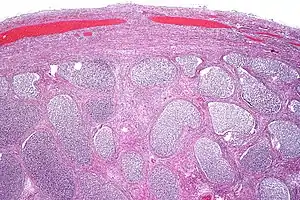

Scrotal ultrasound showing calcifications and cysts in a case of chronic epididymis.

Chronic infectious epididymitis is rare.[18] Some signs and symptoms include localized tenderness and swelling in the epididymis, which are different from any tenderness/abnormality present in the testis, these are usually not found in lower urinary tract. Chronic infectious epididymitis may be diagnosed in healthy adolescents as well as men. Some factors that predispose individuals to chronic infectious epididymitis include sexual activity, heavy physical exertion, and bicycle or motorcycle riding.[19] Those diagnosed with chronic or recurrent epididymitis should receive a CT scan with contrast and a prostate ultrasonography to rule out structural abnormality of the urinary tract. If suspected to have chronic infectious epididymitis, consider getting a urinalysis, urine culture, and urine nucleic acid amplification tests for presence of Neisseria gonorrhoeae and Chlamydia trachomatis.[16] Management of chronic infectious epididymitis is similar to management of acute infectious epididymitis, rarely does treatment extend to surgical management.[17]